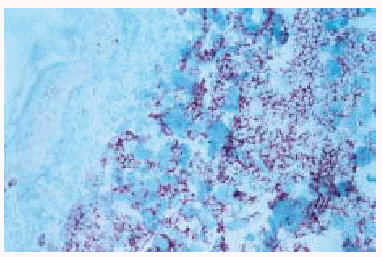

Fig. 5.--Positividad del infiltrado para la tinción con CD43.

Fig. 6.--Positividad del infiltrado en la tinción con MIB-1, lo que demuestra un alto índice proliferativo.